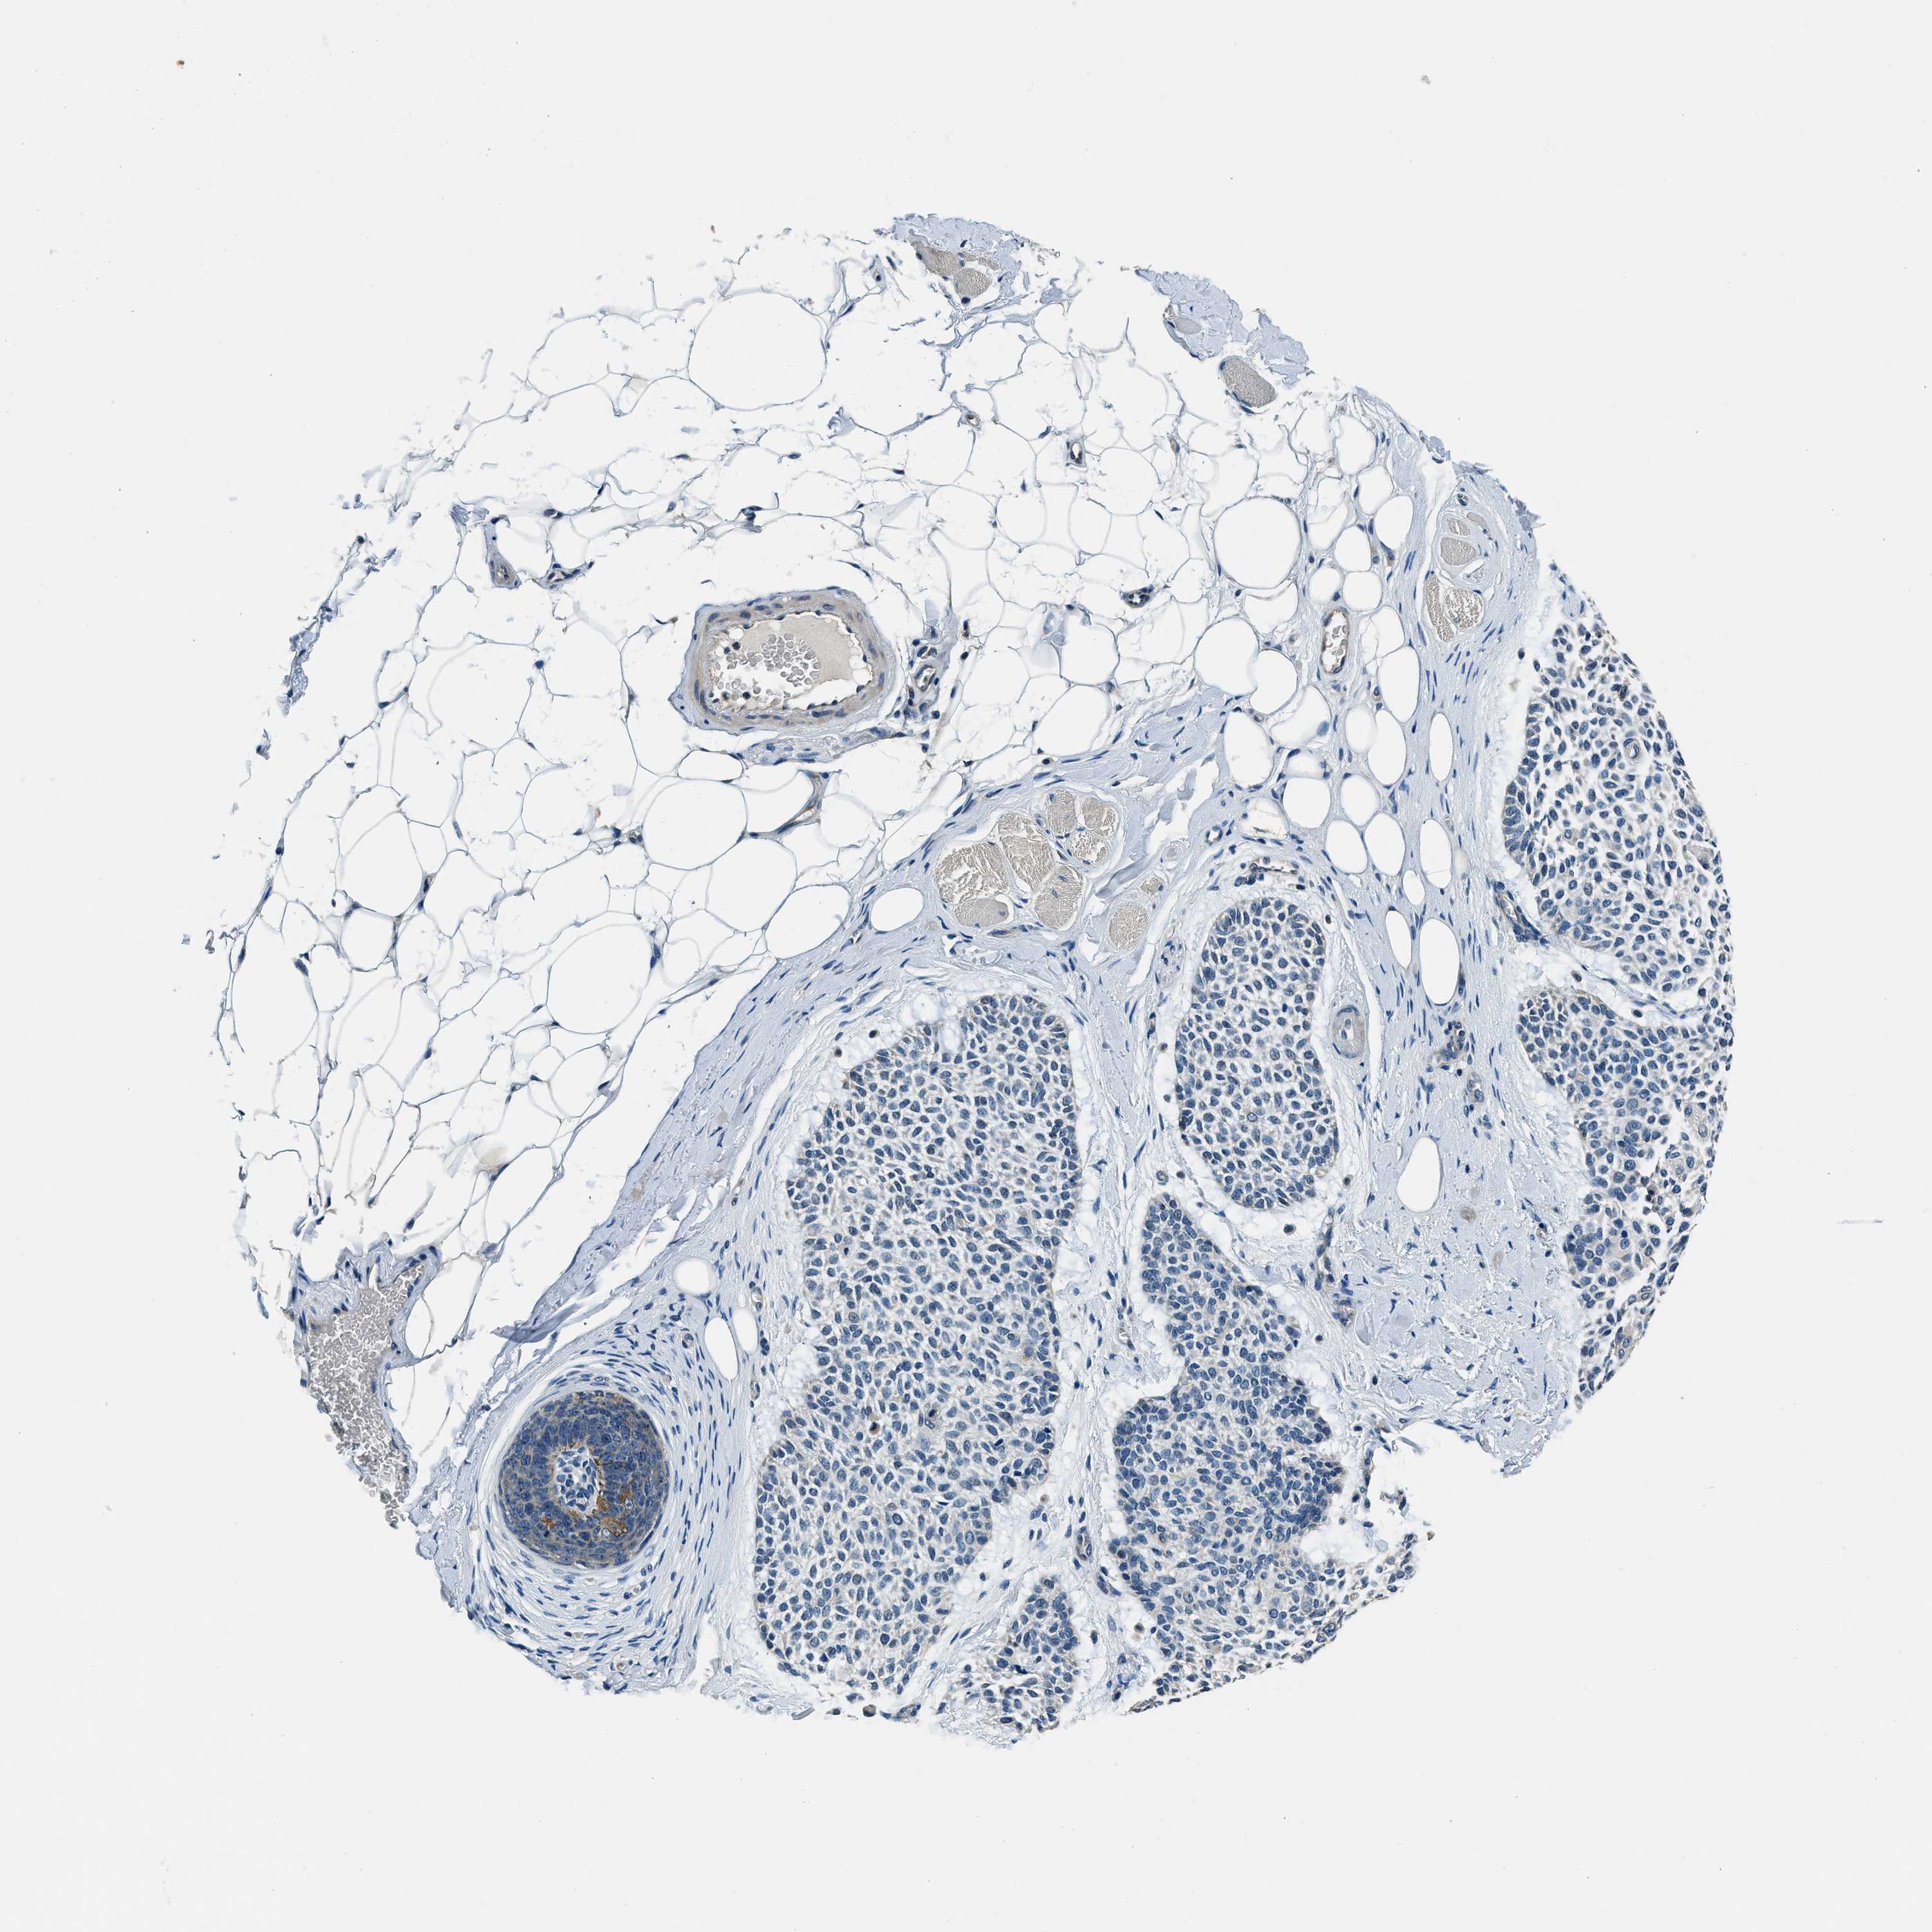

Basal cell and squamous cell cancer

SKIN CANCER - Protein expressioni

A mouse-over function shows sample information and annotation data. Click on an image to view it in a full screen mode. Samples can be filtered based on level of antibody staining by selecting one or several of the following categories: high, medium, low and not detected. The assay and annotation is described here.

Each image is clickable and will lead to virtual microscopy that enables deeper exploration of all samples and also displays staining intensity scores, fraction scores and subcellular localization as well as patient and tissue information for each sample.

Antibody HPA019259

Basal cell carcinoma